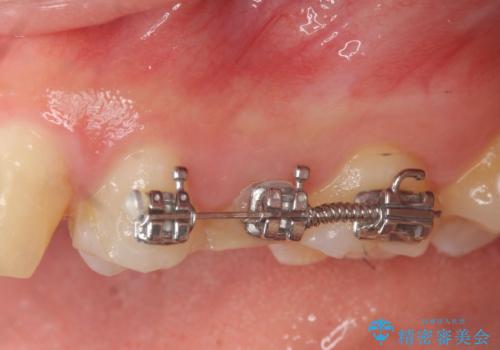

- 部分ワイヤー矯正

虫歯が大きかったことから、神経の温存はできたものの歯ぐきよりも深い虫歯の問題を解決するため、部分矯正治療を併用したセラミック治療を行うこととしました。

当初、歯ぐきよりも深い虫歯の存在や、歯のポジションに問題がありましたがマルチブラケットを用いた部分矯正で行うことで歯の挺出同時に適切な位置へと歯を移動させ、歯周環境を整えたセラミック治療を行うことができました。